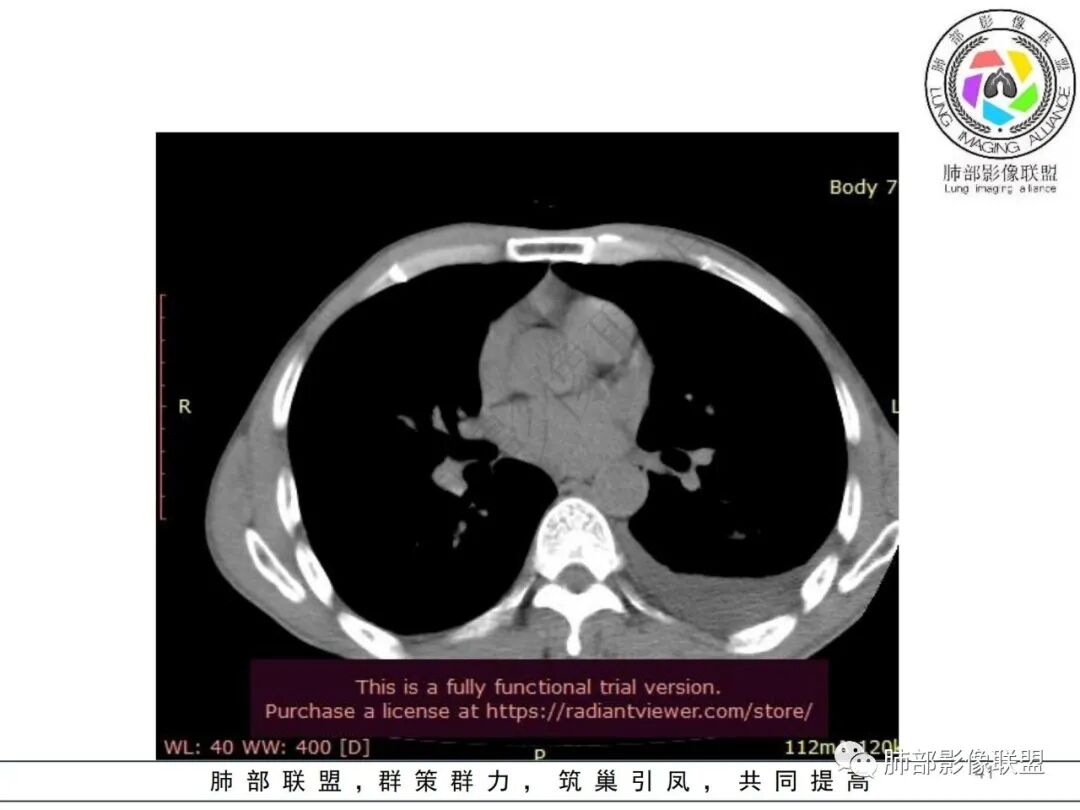

但是肺克肝脓肿血播到肺的,看过很多,没有类似晨读那样表现的,今天晨读不是太典型的血播影像表现;复查的影像就很典型

早上这里是支持血播的

这些层面又像气道

觉得后面那些符合血道,左下的更符合气道的

目前大家支持的观点:肠道来源,肺血播,累及气道

常规分析:左侧胸水,左下肺病灶大,周围渗出明显,气道壁增厚,内部还无坏死,复查坏死空洞也小

从复查分析,按常规左下病灶比其他大,发病早,应该早空洞,更大才对

现在影像反而空洞小,而且早就累及气道,似乎不大符合常规